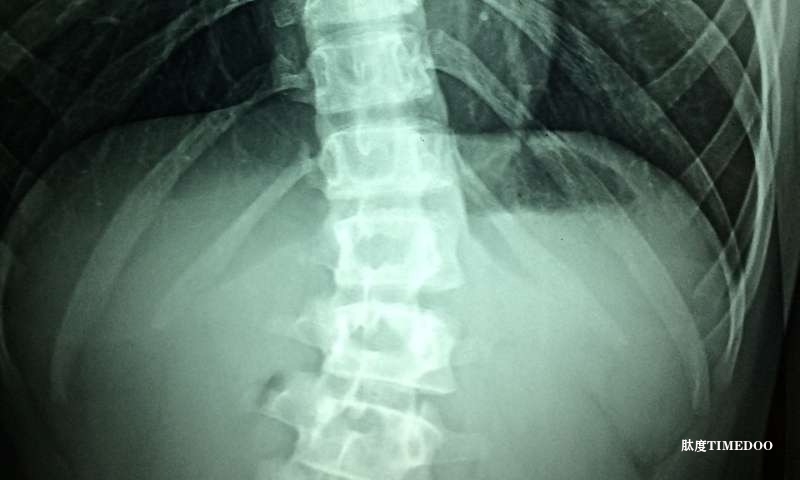

研究團(tuán)隊(duì)在一項(xiàng)小規(guī)模臨床試驗(yàn)中招募了三名輕度SMA患者(3型或4型),為期29天。每位患者在下背部脊髓區(qū)域植入了兩個脊髓電刺激電極,專門刺激感官神經(jīng)根,進(jìn)行為期四小時的治療,每周五次,共進(jìn)行19次治療。